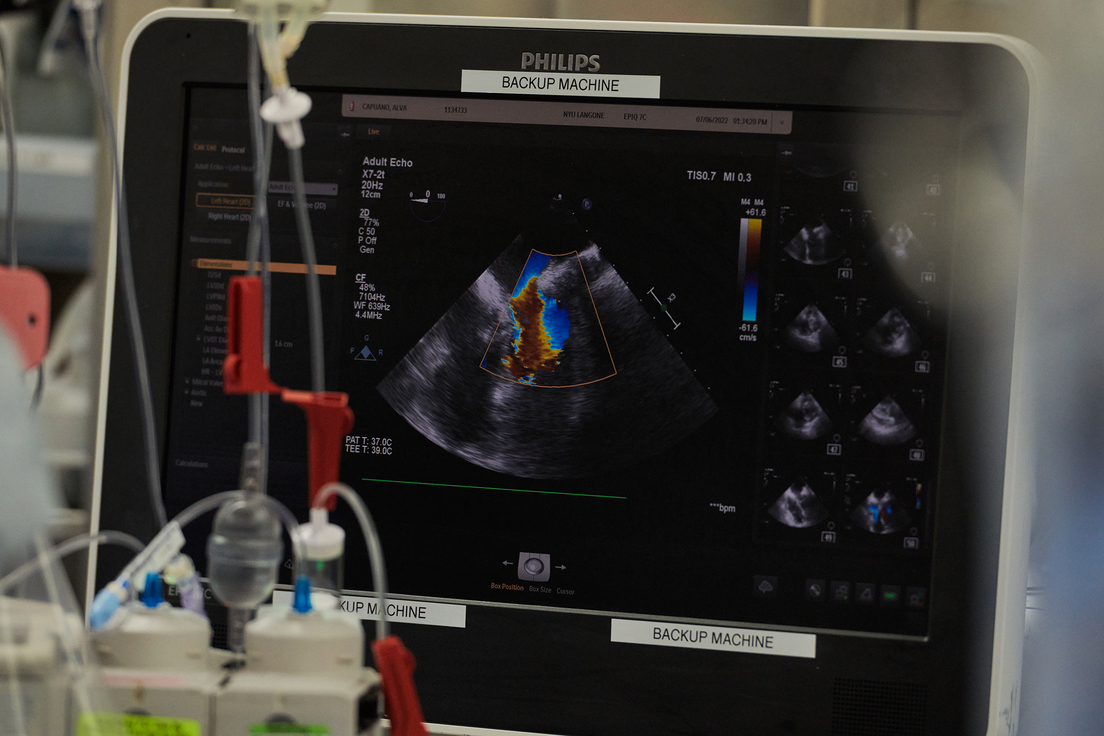

Según los investigadores que llevaron a cabo el procedimiento, los órganos funcionaron normalmente, sin signos de rechazo por parte del organismo, durante los experimentos de tres días en junio y julio. "Pudimos capturar en tiempo real todo lo que estaba pasando durante ese período de 72 horas", afirmó Robert Montgomery, el director del Instituto de Trasplantes Langone de la universidad neoyorquina, en una conferencia de prensa este martes citado por Reuters.

Asimismo, los corazones no mostraron evidencia de un virus porcino que se cree que podría haber contribuido a la muerte del hombre de 57 años que participó del primer trasplante de un corazón de cerdo a principios de año.